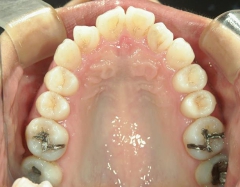

矯正歯科 治療前

矯正_灰色.pngno.41_ 8994_治療前_上.JPG矯正_灰色.png